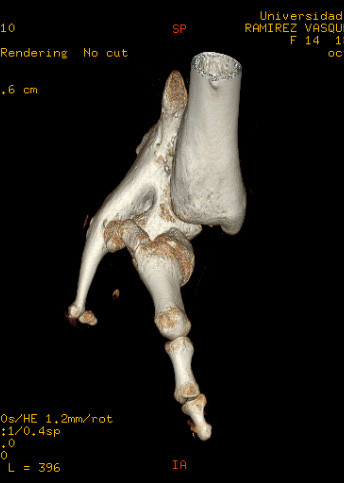

En caso de que el médico cirujano o institución solicitante posea alguna capacidad de impresión 3D, nosotros ofrecemos el servicio de generación de los archivos en formato STL (stereolithography) necesarios para imprimir una pieza ósea en una impresora 3D.

En caso de que el médico cirujano o institución solicitante posea alguna capacidad de impresión 3D, nosotros podemos ofrecer el servicio de generación de los archivos con formato STL (stereolithography) necesarios para imprimir una pieza ósea en una impresora 3D. Los archivos STL también son usados para generar modelos computacionales de las piezas óseas tanto para visualización como para simulación computacional.